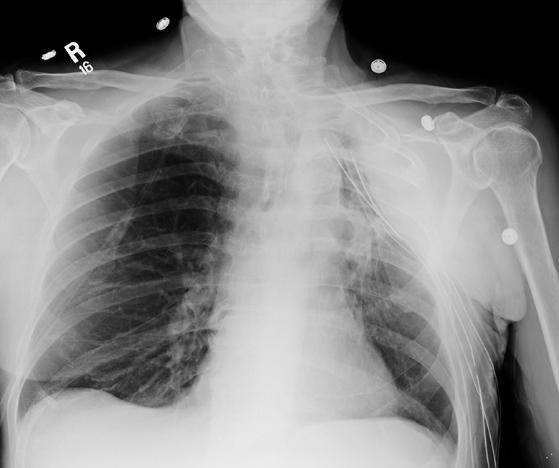

This image is likely a portable radiograph, as the positioning is not good and the patient has so many tubes, it is probably hard to move him. One of the tubes is not in good position, as the side hole is outside the ribs. Check the labels to see where the problem is.

The ideal position of the tip of a chest tube depends on what it was placed for--if it is intended to drain air, the tip should be near the lung apex; if it was placed to drain fluid, the tip is usually inferiorly located in the pleural space; if it is intended to drain a specific loculated fluid collection (fluid that is not free flowing but is encapsulated in one part of the pleural space, usually by fibrosis or adhesions), then the tip should be positioned within the fluid collection. In this case, the fluid collection is lateral to all of the tubes, but may eventually be drained as two of them are close in position. The problem tube has its side hole outside the ribcage, and therefore it will not function well and should be repositioned.